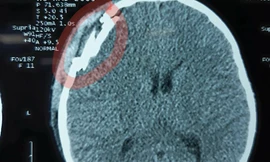

TPO - Ngày 26/11, BS Nguyễn Quang Hưng, Đơn vị Ngoại Thần kinh, Khoa Ngoại tổng hợp Bệnh viện Đa khoa S.I.S Cần Thơ cho biết, tại đây vừa can thiệp loại bỏ khối u não kích thước lớn cho bệnh nhân. Đây là trường hợp rất hy hữu, người bệnh tình cờ phát hiện khối u khi kiểm tra chấn thương vùng đầu sau tai nạn giao thông.

TPO - Lúc 23h ngày 22/3, tại Bệnh viện Chợ Rẫy (Thành phố Hồ Chí Minh), ông Huỳnh Văn Nén, “người tù thế kỷ” đang được chụp cắt lớp (CT) để xác định tình trạng chấn thương sọ não. Bà Nguyễn Thị Cẩm, vợ ông Nén cho biết.